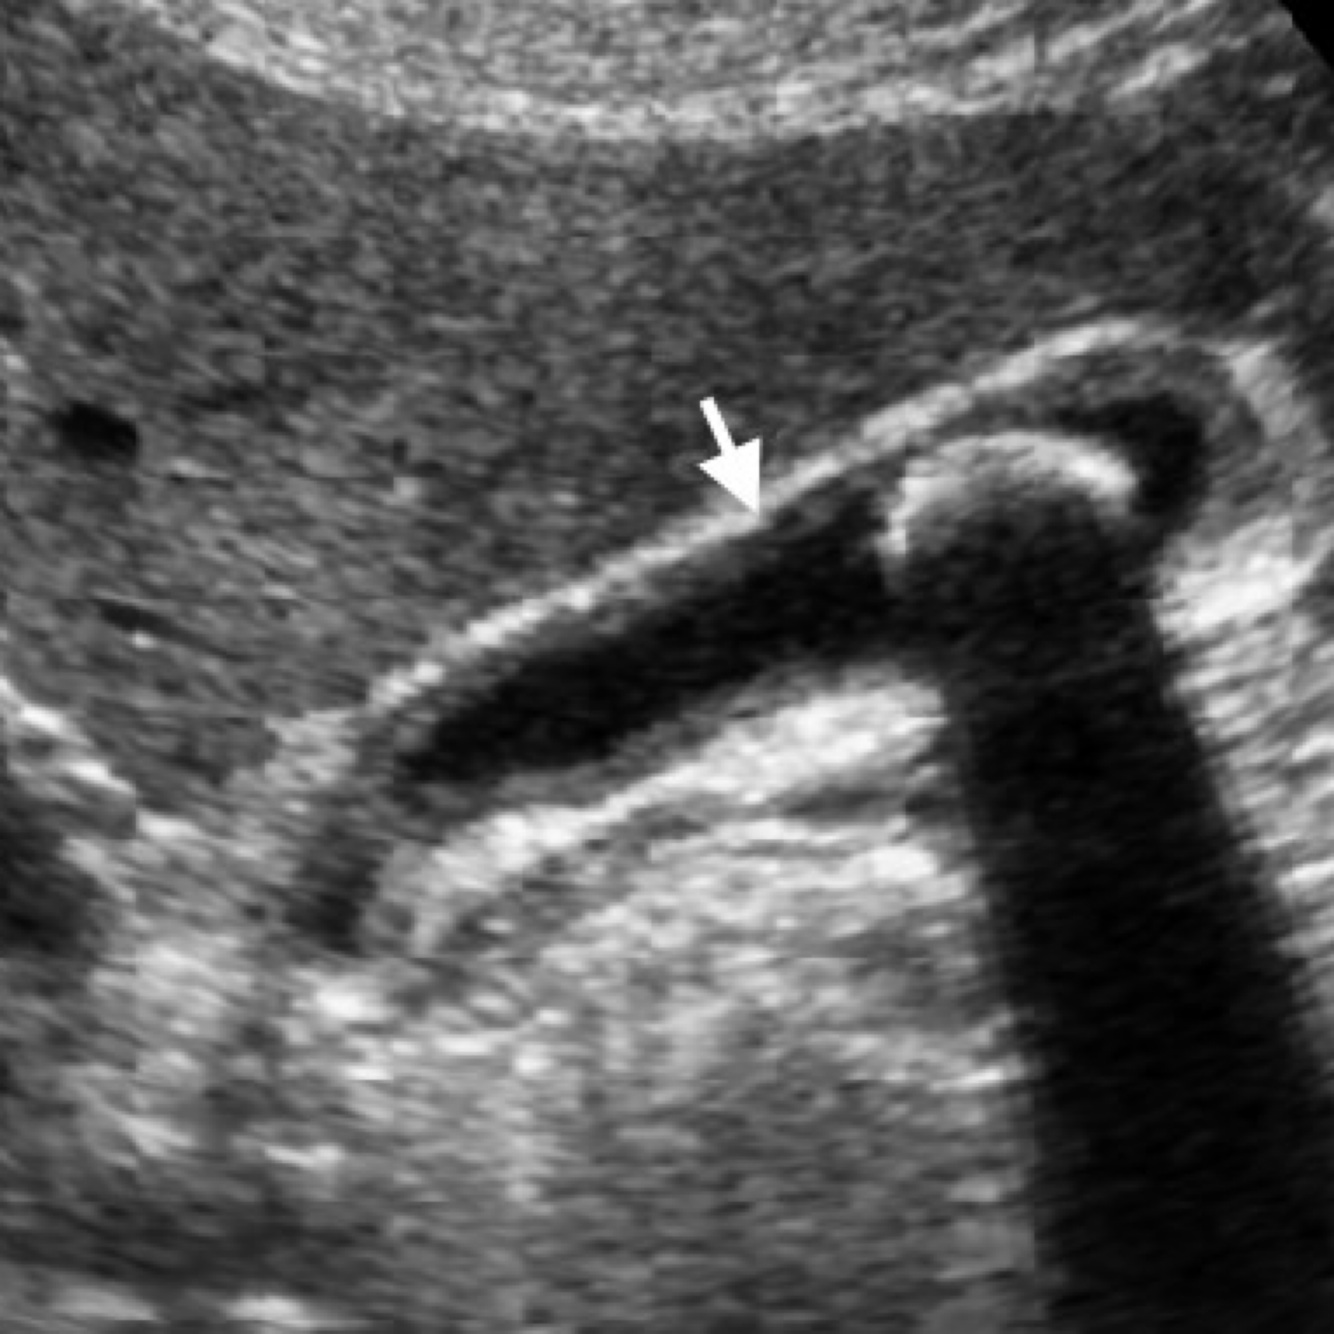

A

Wall-Echo-Shadow Triad

●With careful technique, visualize wall–echo–shadow (WES) triad or double-arc shadow sign.

●First arc or curved echogenic line represents thickened GB wall.

●Second arc is from surface of stone followed by posterior acoustic shadowing.

●With chronic disease, GB may be so contracted and is difficult to visualize.

●WES sign can be mimicked by residual barium, a porcelain gallbladder, or Bouveret syndrome.

●Air-filled bowel loops in RUQ may create shadowing which can be mistaken for contracted GB with stones.

●Differential diagnosis for chronic cholecystitis is adenomyomatosis and GB carcinoma.